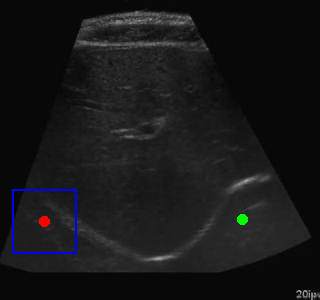

Segmentation Example Segmentation Example Segmentation Example

Example of segmentation results on an abdominal ultrasound image. The top left in the above is the orginal cropped image of the Ultrasound , the top right shows the mask_cropped image after the segmentation . Then combining these two we get our overalled_cropped image where the red overlay shows the segmented region of interest.